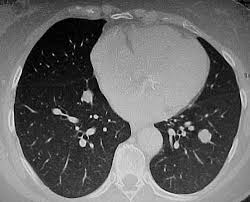

Ciò è fondamentalmente legato al fatto che nella valutazione tc dei linfonodi mediastinici la maggior parte degli studi usa la grandezza del linfonodo (diametro corto >10 mm) come unico criterio suggestivo di malignità, limitando così l'utilità di questo metodo a confronto con la pet6. 10 riscontri mediastinici linfonodi arteria polmonare esofago sarcoidosi toracica. Chi non ha una conoscenza approfondita del corpo umano difficilmente ha sentito parlare del mediastino, anche se è una parte fondamentale.

Tc linfonodi mediastinici / ilari ingranditi non visibili alla radiografia del torace in pazienti non affetti da cancro: Si tratta infatti dello spazio posto all'interno della gabbia toracica, incassato tra le cavità pleuriche e i polmoni di lato. 10 mm per i linfonodi ovoidali, 8 mm per quelli arrotondati.